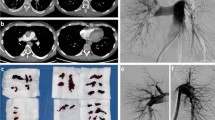

Mechanical thrombectomy was achieved using the FlowTriever System via large-bore transfemoral venous access. Full details of the procedure have been reported previously [11]. In brief, the Triever Catheter (16, 20, or 24 Fr) was advanced over an 0.035” guidewire into the pulmonary arteries for thrombus aspiration. If needed, the FlowTriever Catheter was advanced through the Triever Catheter over the guidewire for mechanical thrombus dislodgment and removal. Pulmonary angiography and right heart catheterization were performed immediately before and after the thrombectomy. A suture-based closure device was used. Procedure time was defined as the time from gaining venous access until sheath removal.

From April 2021 to August 2022, 29 patients (34% female) were included. The patients’ baseline characteristics are summarized in Table 1. Most patients were at high (17%) or intermediate-high (76%) risk, according to the 2019 ESC acute PE Guidelines [3]. The mean PE severity index (PESI) [13] was 121 ± 38. Bilateral PE occurred in 79% of the patients. The median time from the symptom onset to the procedure was 21 h (IQR: 4–24). The median procedural time was 68 min (IQR: 60–90). The procedural characteristics are summarized in Table 2. The median ICU and in-hospital length of stay were 2 days (IQR: 1–4) and 7 days (IQR: 6–11), respectively. At discharge, 83% of the patients were prescribed direct oral anticoagulants, 3% vitamin K antagonists, and 14% low-molecular-weight heparin (Table 2).

Table 3 summarizes the invasive and non-invasive hemodynamic data. Before thrombectomy, mean sPAP (51.3 ± 11.6 mmHg) and mPAP (29.8 ± 9.1 mmHg) were severely elevated. On table, mean sPAP, diastolic PAP (dPAP), and mPAP dropped by -15.0 mmHg (95%: -18.9 to -11.0; p < 0.001) (Fig. 1), -3.8 mmHg (95% CI: -6.6 to -1.1; p = 0.008), and − 8.4 mmHg (95% CI: -11.0 to -5.8; p < 0.001), respectively. While 2 (7%) patients had an sPAP > 70 mmHg before thrombectomy, none of the patients had an sPAP > 70 mmHg post-thrombectomy.

From post-thrombectomy to three months, mean sPAP (p = 0.002) continued to decrease (Table 3). Compared with before thrombectomy, sPAP (-23.2 mmHg, 95% CI: -28.5 to -17.8; p < 0.001), dPAP (-6.7 mmHg, 95% CI: -11.6 to -1.8; p = 0.010), and mPAP (-12.0 mmHg, 95% CI: -16.8 to -7.2; p < 0.001) were significantly lower at three months. The change in sPAP from pre-thrombectomy to post-thrombectomy (r=-0.76; p < 0.001) and three months (r=-0.80; p < 0.001) strongly correlated with the pre-thrombectomy sPAP (Fig. 2). The proportion of patients with mPAP ≤ 20 mmHg increased on table and continued to increase until three months (Cochran’s Q p = 0.001) (Fig. 3).